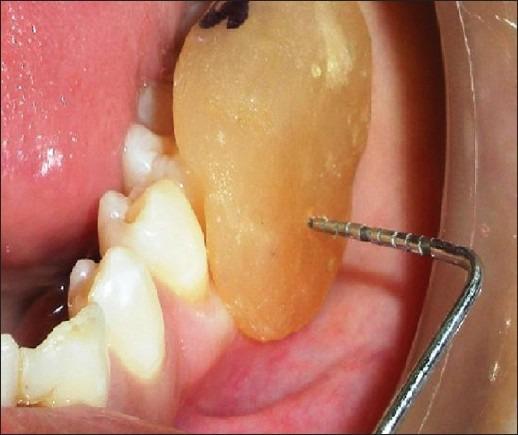

The present study was undertaken to evaluate the effectiveness of the combination of hydroxyapatite and β-tricalcium phosphate bone alloplast with bioresorbable guided tissue regeneration membrane for the treatment of mandibular grade II furcation defects.

A total of eight patients, four females and four males, in the age group of 18 to 65 years, with bilateral buccal grade II furcation defects in the mandibular molars, participated in the study.

The mean gain in the relative clinical attachment levels in the test and control groups, at the end of six months, were 2.50 and 1.63 mm, respectively. The mean change in the horizontal probing depth values at the end of six months in the test and control groups were 2.88 and 1.63 mm, respectively. The mean reduction in the vertical probing depth values in the test and control groups were 1.50 and 1.38 mm, respectively.

The resorbable GTR membrane with bone material was more effective than open debridement alone, in the treatment of furcation defects.